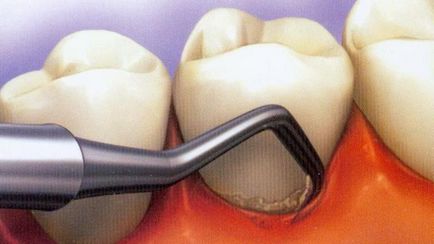

Atribuite pentru a elimina subgingivala microbiană placa și granularea tisulară a buzunarelor.

Pe măsură ce procedura se face? Asistenta pune o anestezie regională locală și medicul începe curățarea buzunarele cu mâna sau instrumente cu ultrasunete. Dentistul indeparteaza cu atentie depozitele moi si dure subgingivale, arată adânc în fiecare buzunar, scoate-l din țesutul de înlocuire cavitatea și masa patologică. cavitate purificată a fost spălată cu o soluție izotonică pe bază de clorură de sodiu. Medicul lustruiește apoi rădăcinile dintelui.